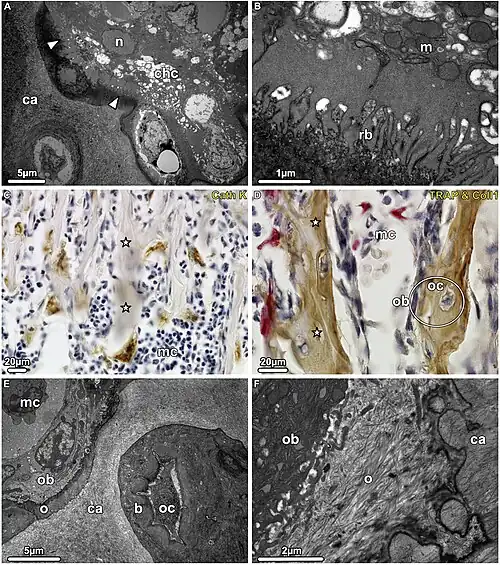

Een chondroclast is een meerkernige reuscel die deelneemt aan de kraakbeenresorptie.[1] De cel is TRAP-positief (Tartrate-resistant Acid Phosphatase) en morfologisch niet te onderscheiden van de osteoclast. Morfometrische evaluatie toonde echter aan dat chondroclasten geen gegolfde randen en heldere zones vormen, d.w.z. bekende resorptiekarakteristieken, in dezelfde mate als osteoclasten, aanwezig bij de lagere metafyse. In plaats daarvan hebben chondroclasten de neiging om een ongedifferentieerd oppervlak te vertonen grenzend aan de matrix, dat structureel niet verschilt van het basolaterale celmembraan.[2] De chondroclast/osteoclast is afkomstig van stamcellen uit het beenmerg. Ze ontstaan uit de fusie van monocyten.

Chondroclasten en osteoclasten zijn transcriptioneel ook verschillende celpopulaties en vertonen discrete transcriptomische kenmerken. Moleculaire reactiepaden zijn specifiek voor chondroclasten en osteoclasten. Chondroclasten en osteoclasten hebben subsets van metabolische genen die specifiek zijn voor chondroclasten. De eiwit-eiwitinteractie-netwerkanalyse toont een overvloed aan gestructureerde netwerken van metabolische reactiepaden, ATP-synthese en proteasoomreactiepaden in chondroclasten. De genregulerende netwerkanalyse met behulp van het transcriptiefactor-doelgennetwerk voorspelt een pool van genen, waaronder ETV6, SIRT1 en ATF1 als chondroclast-specifieke gensignatuur.[3] Een gen (of genetisch) regulerend netwerk is een verzameling moleculaire regulatoren die met elkaar en met andere stoffen in de cel interacteren om de genexpressieniveaus van mRNA en eiwitten te regelen, die op hun beurt de functie van de cel bepalen. Gen (of genetisch) regulerende netwerken spelen ook een centrale rol in de morfogenese.

Direct contact van chondroclasten/osteoclasten met het verkalkte kraakbeen kan cruciaal zijn voor normale endochondrale ossificatie.

Resorptie van niet-gemineraliseerd subchondraal kraakbeen door chondroclasten en macrofagen kan een kenmerk zijn van gewrichtsdestructie bij ontsteking en niet-ontsteking gerelateerde artropathieën, evenals bij ontsteking en neoplastische subchondrale gerelateerde botlaesies.[4]